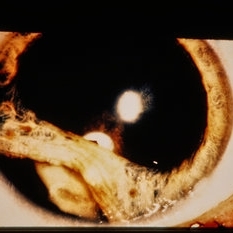

Pre-retinal and retinal hemorrhage with foreign body.

Condition/keywords: intraocular foreign body, trauma